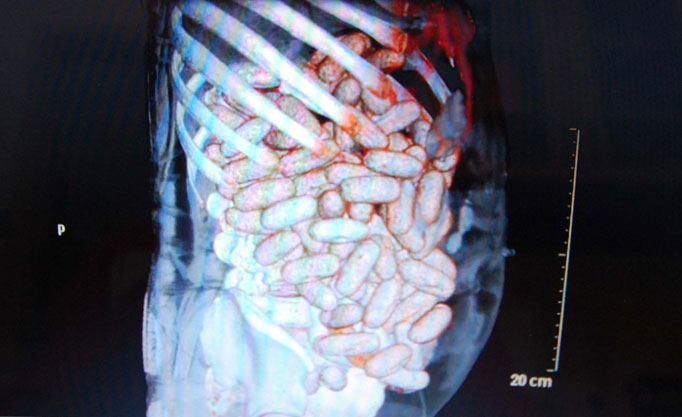

Kinh hoàng người đàn ông chứa 2 kg cocaine trong bụng